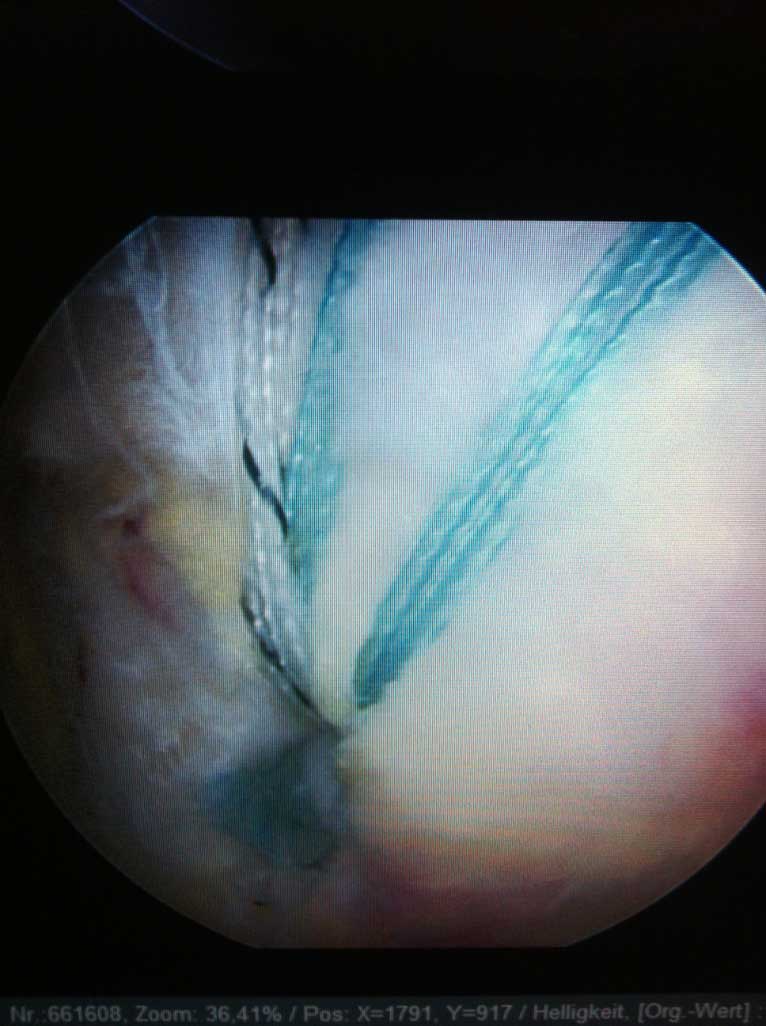

Wie auf der Bilddokumentation ersichtlich, wird die Kontaktfläche zwischen der kleinen knöchernen Pfanne und dem Kopf durch einen knorpeligen Ring, s.g. Labrum, der sich am Pfannenrand befindet, vergrössert.

Je nach Alter, Verletzungsmuster, Anzahl der Luxationsereingnisse und weiteren Faktoren, wird eine schulterstabilisierende Operation indiziert und empfohlen. Diese führen wir ebenfalls ausschliesslich arthroskopisch

(Schüsselloch Operation) durch. Innerhalb von 15 - 30 min wird dabei der knorpelige Ring (s.g. Labrum) auf den knöchernen Pfannenrand mit speziellen Anker und Fäden wieder zurück befestigt.